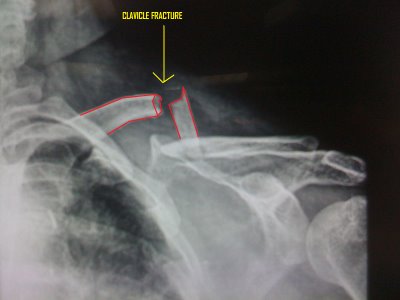

Frattura comminuta della clavicola - DocCheck

Frattura comminuta della clavicola - DocCheck from dccdn.de